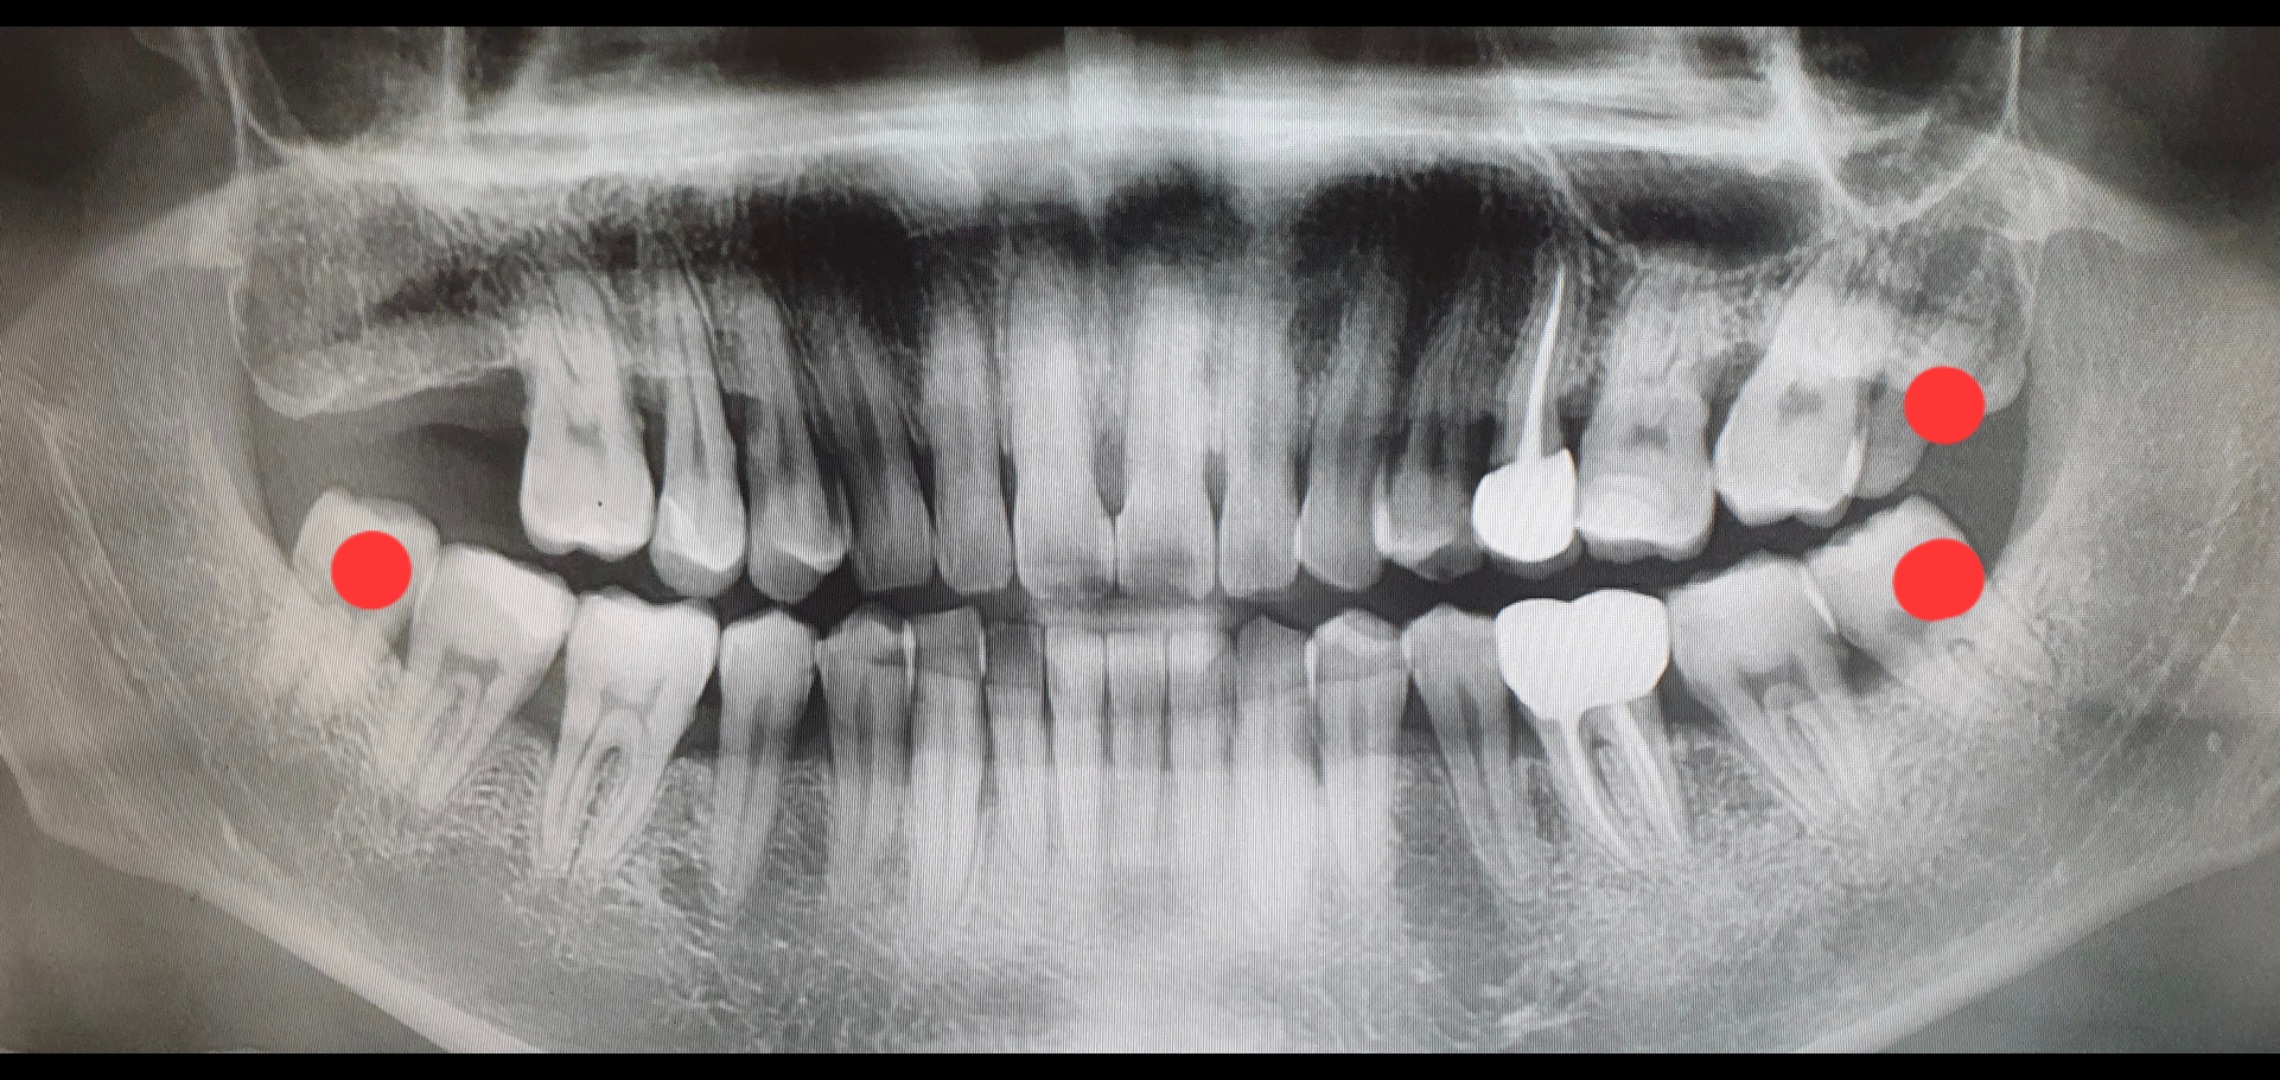

며칠 전 사랑니를 뽑았다.

의사선생님은 안뽑아도 되지만 뽑고 싶으면 뽑아주겠다길레 나는 뽑겠다고 했다.

항상 혓바닥으로 입속을 훑을 때마다 '나는 왜이렇게 이빨이 많을까' 생각을 하곤 했는데, 범인은 사랑니였다.

뽑아야할 사랑니는 총 3개다. 오른쪽 2개, 왼쪽 1개. 다들 어금니 코스프레 하고 있다.

치과 체어에서 대기하는 동안

내 앞의 모니터에 떠있는 내 엑스레이(CT?) 사진을 폰으로 찍었다.

빨간 점으로 표시한게 사랑니들이다. 오른쪽 2개는 며칠전 뽑아서 잘 아물고 있고,

다음주 목요일에 왼쪽 남은 하나를 마저 뽑을 예정이다.